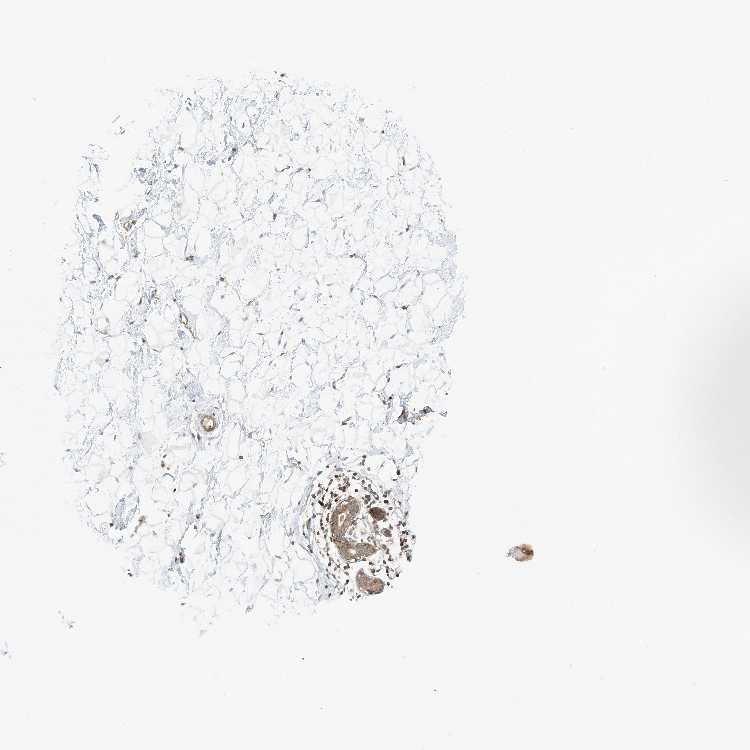

BREAST - Antibody stainingi

Antibody staining in the annotated cell types in the current human tissue is reported as not detected, low, medium, or high, based on conventional immunohistochemistry profiling in selected tissues. This score is based on the combination of the staining intensity and fraction of stained cells.

Each image is clickable and will lead to virtual microscopy that enables deeper exploration of all samples and also displays staining intensity scores, fraction scores and subcellular localization as well as patient and tissue information for each sample.

Antibody HPA035241

Adipocytes Not detected

Glandular cells Medium

Myoepithelial cells Medium